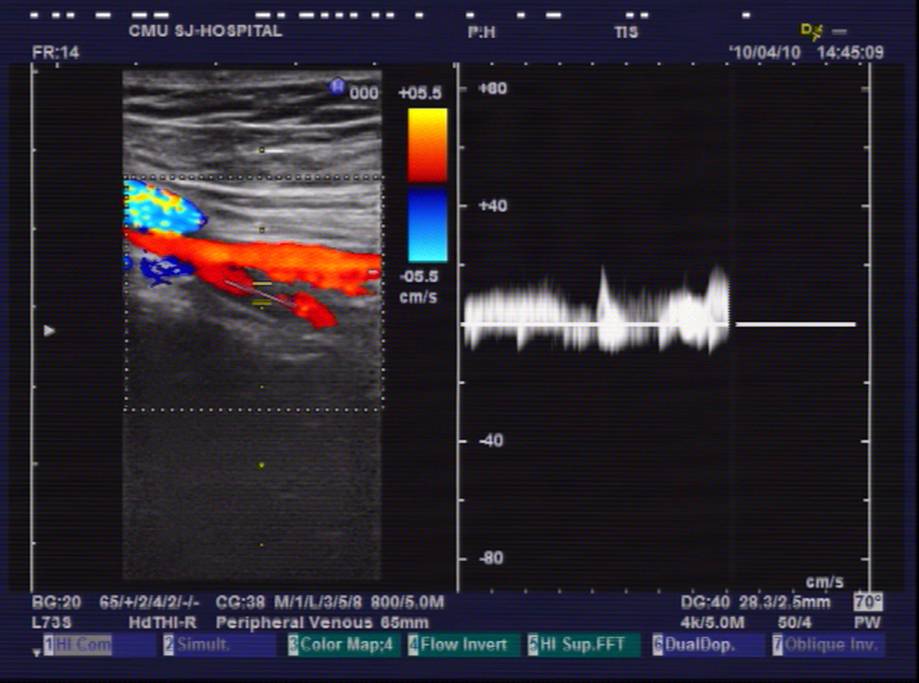

超声图像1

患者女性,52岁,因右膝关节疼痛2月为主诉入院。入院根据病史、查体和X线片诊断为右膝骨关节炎,经常规入院检查,未发现手术禁忌症,在硬膜外麻醉下行关节镜清理手术。术中应用止血带止血,手术过程顺利,手术时间为35分钟。术后给予弹力绷带包扎右下肢,术后第一天即嘱病人下地活动,疼痛较术前明显好转。术后给予了抗生素等药物,但未应用抗凝药物。术后第三天,患者出现右下肢肿胀、胸痛、呼吸困难,经行下肢超声和肺CT检查,结合血气分析等指标,呼吸科诊断为右下肢深静脉血栓形成,肺栓塞,转入呼吸科治疗。经溶栓、抗凝、支持等治疗2周后,病情痊愈出院。出院后继续服用华法林,定期检查凝血功能,维持INR值在1.5-1.5。